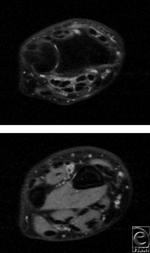

Two months later, he underwent left lateral epicondylectomy with suture-repair of the extensor digitorum communis to the extensor carpi radialis longus. At his 1-month follow-up, the patient had a new onset left dorsal wrist pain and the inability to extend the thumb IPJ. Magnetic resonance imaging confirmed rupture of the EPL tendon at the third compartment (Fig 4). The patient was taken to the operating room where EPL reconstruction with a palmaris tendon graft was performed. At the patient's 1-month follow-up, elbow pain had resolved and full EPL function returned.

![]() |

| Figure 4. T2-weighted MRI images of patient 3 demonstrate inflammation and the absence of a tendon within the third dorsal compartment. MRI indicates magnetic resonance imaging. |